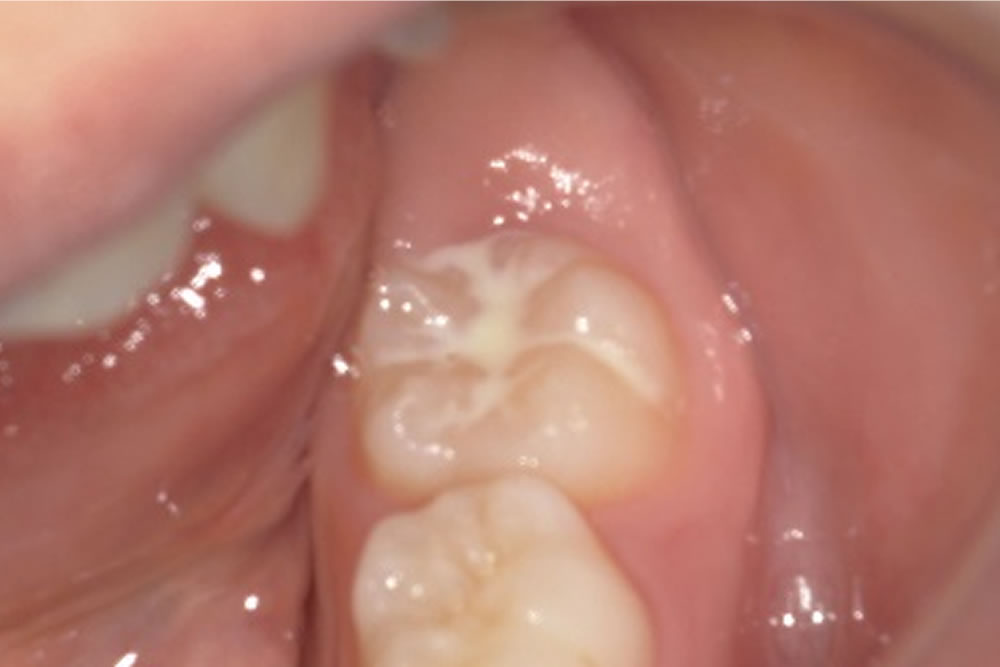

子供の虫歯予防対策「シーラント」を実施した症例

▼当院で実施したシーラントの症例をご紹介します。

処置前の口腔内

右下の6才臼歯(5~6才頃に生える初めての永久歯)に対し、シーラントを行います。シーラントとは、フッ素入りの乳白色の樹脂を歯の溝に埋める処置です。

生え変わったばかりの永久歯は抵抗力が低く、虫歯になりやすいという特徴があります。そのため、歯の溝を予め埋め、食べかすなどの蓄積防止とケアをしやすくすることで虫歯の予防リスクを軽減します。

シーラントの実施

| 年齢・性別 | 10代 女性 |

|---|---|

| 治療期間 | 1日 |

| 治療回数 | 1回 |

| 治療費 | 保険適用 |

| リスクなど | ・処置後すぐに食事をすると、外れてしまう場合がある。 ・日々のケアを怠ると虫歯になる可能性がある。 |